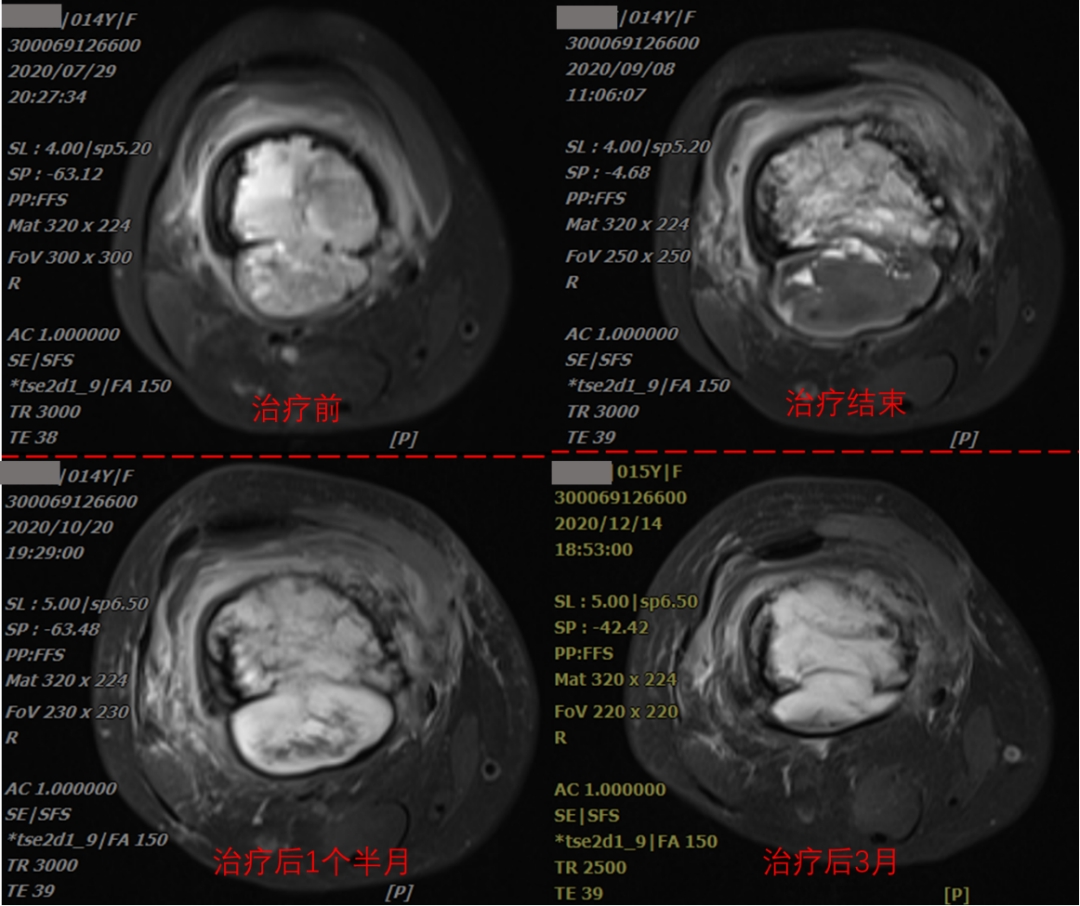

The patient, a 14-year-old female, was presented with the main complaint of "right thigh pain with mobility disorder for 3 months". CT examination indicated mild dilatant bone destruction in the right lower femur, accompanied by periosteum hyperplasia and soft tissue swelling, and neoplastic lesions (about 3.6x12.1x4.9cm in size) were mainly considered. Biopsy of the right femur mass was performed, and the biopsy results showed osteosarcoma (right lower femur). Diagnosis: osteosarcoma of right femur (cT2N0M0 Stage IIB KPS score: 70). The comprehensive treatment based on carbon ion radiotherapy was started on August 18, 2020. The tumor volume was 188.62cm3, and the heavy ion therapy was completed 12 times in total within three weeks. The treatment will end on September 3, 2020.

As can be seen from imaging data, tumor inactivation and slow absorption after treatment. According to international experience, it may take 1-2 years for huge sarcomas to be completely absorbed after inactivation. However, after heavy ion treatment, the purpose of limb preservation can be achieved, and anti-tumor immunity can be activated, and distant and side effects can be induced, which can effectively remove tumor tissue outside the tumor body. Combined treatment with chemotherapy and immunotherapy is expected to achieve a better effect, providing a new way for osteosarcoma patients. Through the observation of the treatment process of the patient's osteosarcoma, it can be seen that 1 and a half months after the end of heavy ion treatment of osteosarcoma, the local edema of the tumor was obvious, and 3 months after the end of the treatment, the local tumor was significantly smaller than before the treatment, the patient's symptoms were significantly relieved, and the tumor was well controlled locally. During the treatment, there was no obvious pain, no obvious edema in the lower extremities, and no obvious radiotherapy reaction in the local skin.